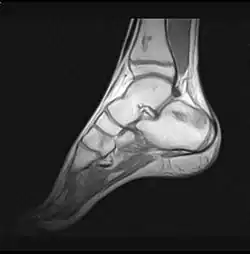

- Stadium ARCO 0

Im Anfangsstadium sind in konventionellen Röntgenaufnahme keine krankhaften Veränderungen zu erkennen. In seltenen Fällen ist eine dezente Auflockerung der Knochenfeinstruktur (Trabekel) in dem betroffenen Areal zu erkennen: das Ausmaß dieser Auflockerung ist jedoch zumeist so gering, dass es nicht sicher erkannt werden kann. In der Kernspintomographie (MRT) ist in diesem Stadium ein Bild analog dem Knochenmarködem (KMÖ, transiente Osteoporose; bone marrow edema, BME) zu erkennen. Unter Verwendung der short tau inversion recovery (STIR) Aufnahmesequenz wird eine Signalhyperintensität (helles Aufleuchten im Graustufen-Kernspinbild) festgestellt (vergleiche Bild 1a und 2 helle Ränder). Eine sichere Unterscheidung zwischen dem prinzipiell reversiblen Bild eines KMÖ/BME und dem Stadium ARCO I einer aseptischen Knochennekrose ist nicht mittels des Kernspintomogramms möglich.

Reversibles Frühstadium (MRT-positiv/reaktive Randzone)

Irreversibles Frühstadium (Röntgen positiv)

Die Diagnostik der aseptischen Knochennekrose umfasst die körperliche Untersuchung des wahrscheinlich betroffenen Gelenkabschnittes mit Funktionstests der Gelenke und Knochen sowie bildgebende Verfahren. In aller Regel gehen krankhaften Knochenveränderungen Belastungen oder Verletzungen der unterschiedlichen Art voraus. Dies ist bei den Knochennekrosen anders, die Beschwerden entwickeln sich schleichend. Konventionelle bildgebende Verfahren wie Röntgenaufnahmen oder die Sonographie ergeben nur dann Hinweise auf die Diagnose, wenn es zu erstem Knochenumbau oder Knochenzerstörung gekommen ist. Beim Einsatz der Kernspintomographie mit Kontrastmittel kann auch dann eine Diagnose gestellt werden, wenn es lediglich zu einer typischen Knochenumbauaktivität gekommen ist.